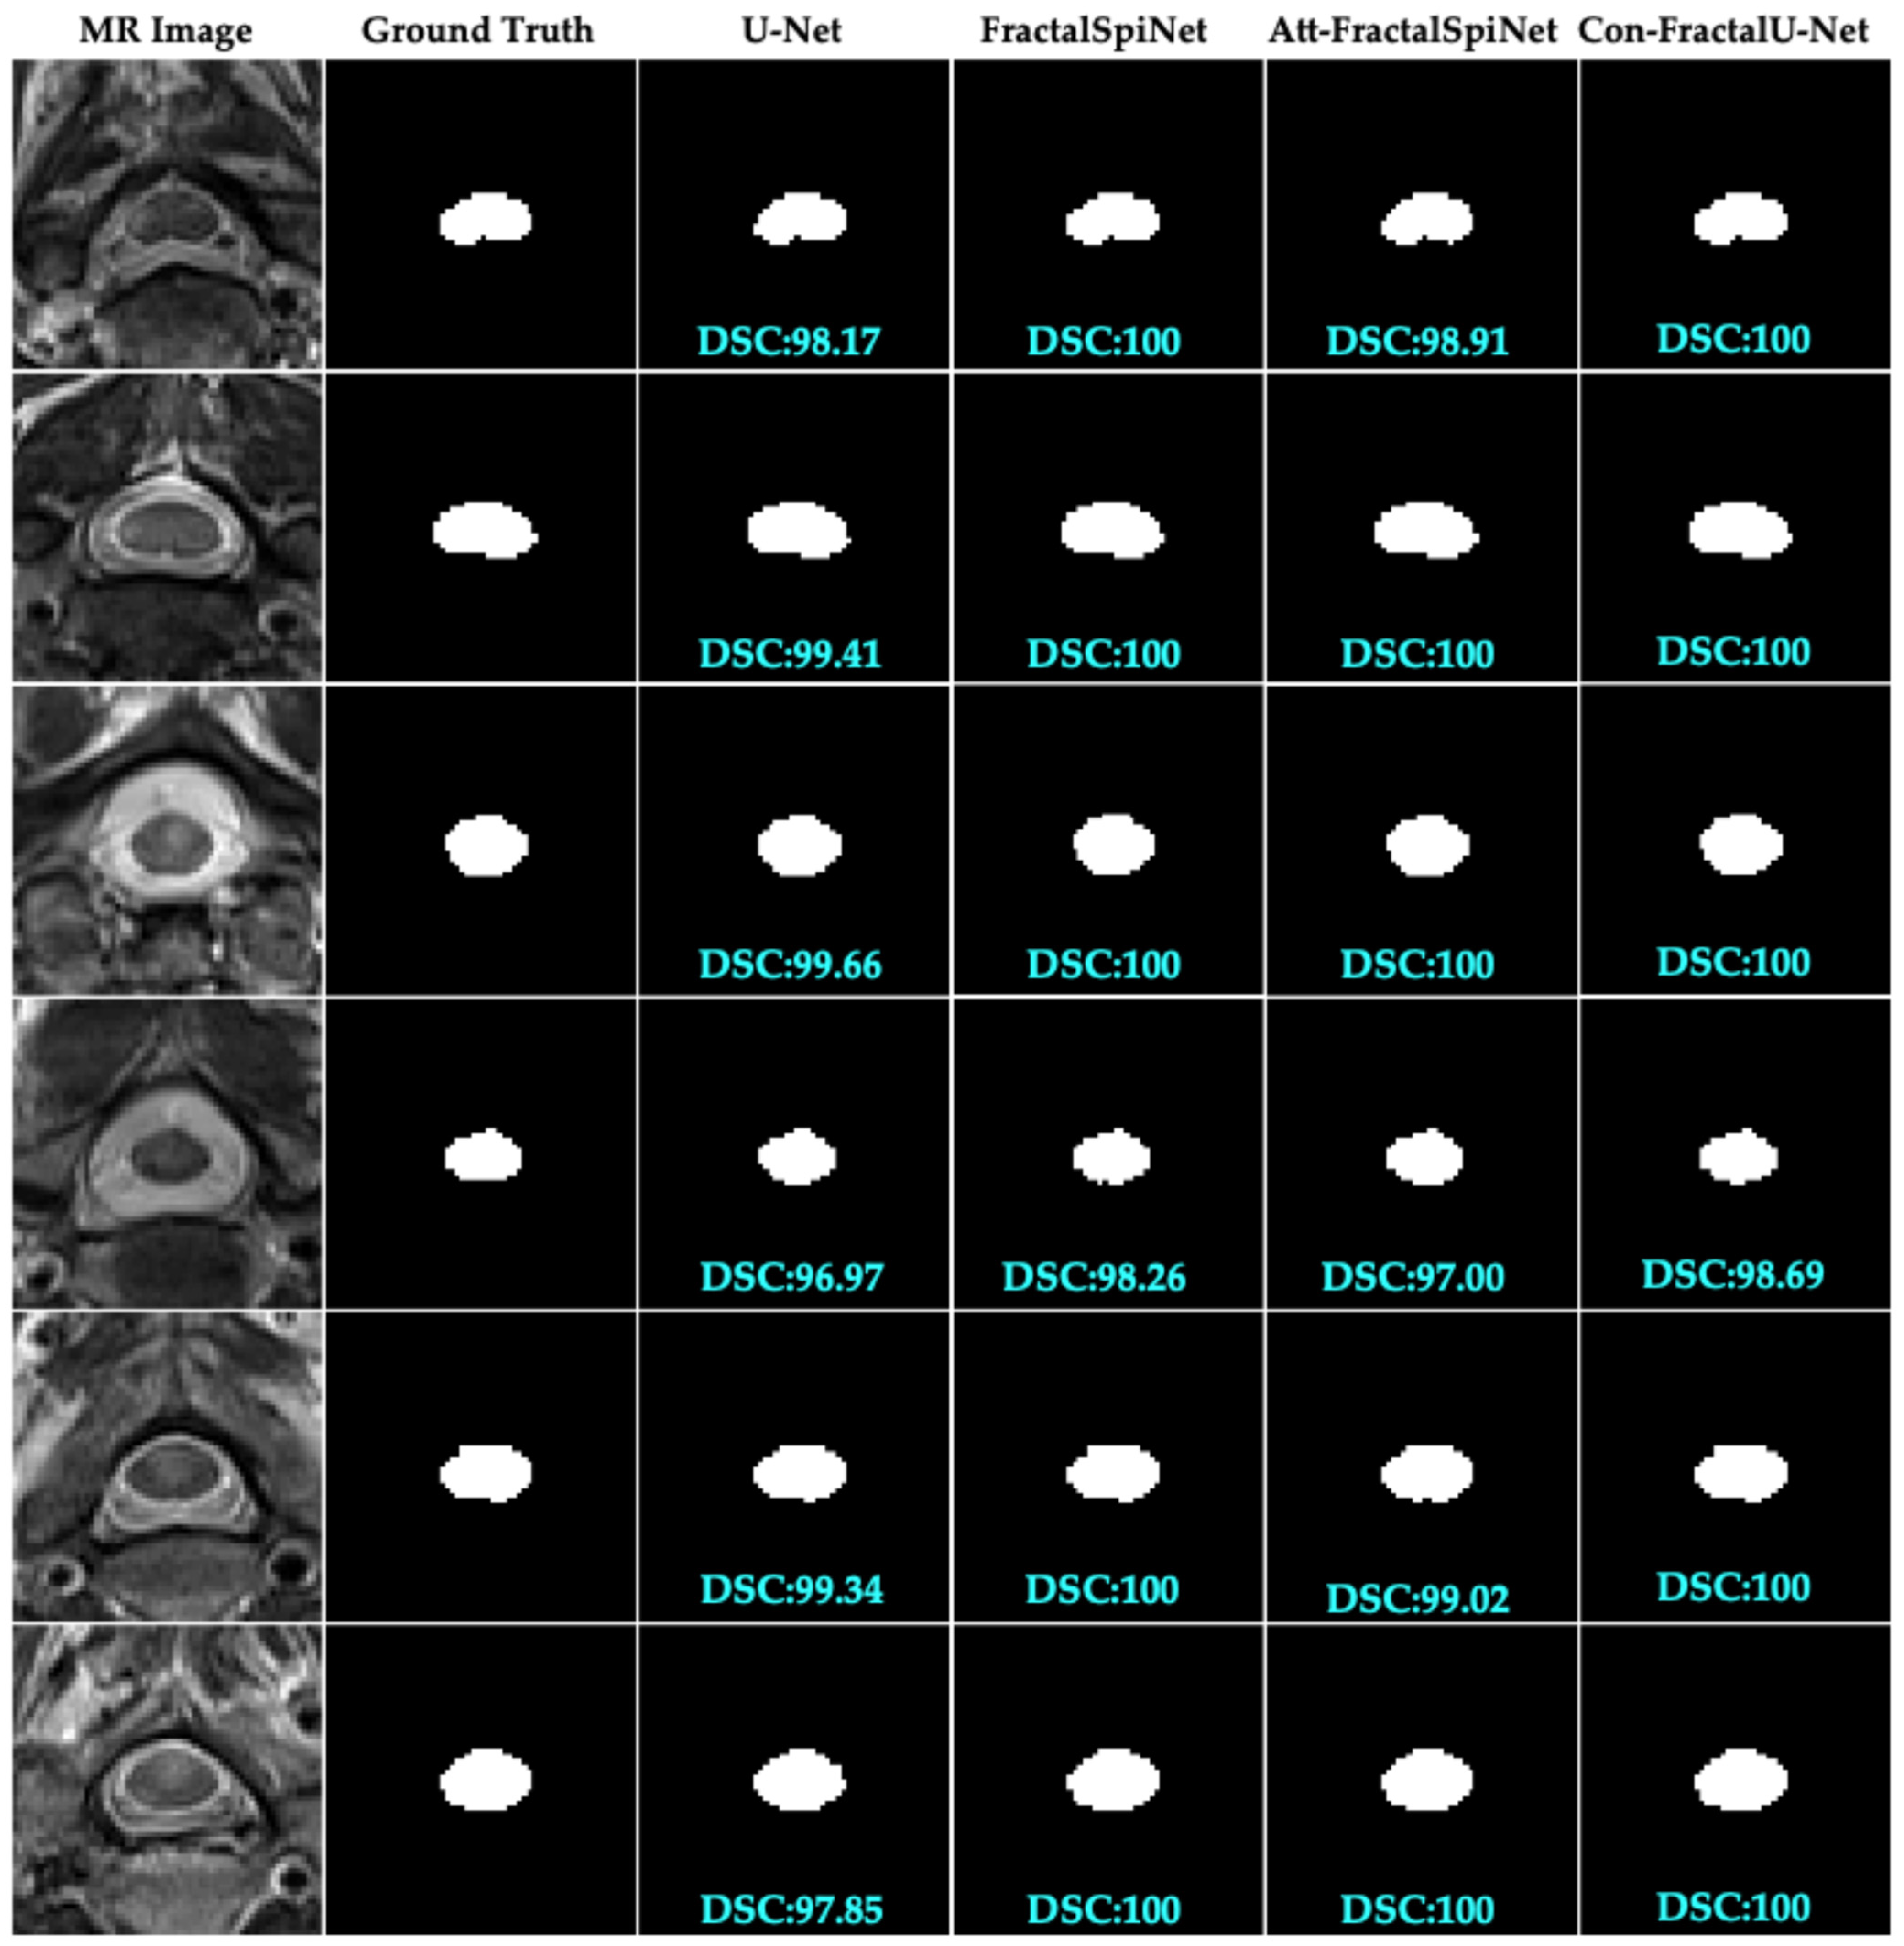

In this study, the performance of different deep learning architectures for the automatic segmentation of MS lesions in the CSC was compared, as shown in Figure 7. The segmentation results obtained using U-Net, FractalSpiNet, FractalSpiNet with an attention mechanism (Att-FractalSpiNet), and FractalU-Net with convolutional blocks (Con-FractalU-Net) architectures were evaluated using the DSC metric. The results revealed that the typical U-Net architecture exhibited relatively lower performance in segmenting MS lesions, while FractalSpiNet and especially Att-FractalSpiNet and Con-FractalU-Net architectures had a significantly better performance. By producing consistent and accurate segmentation results with high DSC values, fractal-based architectures emerge as more promising approaches for automated analysis of MS lesions. Notably, the integration of attention mechanisms and convolutional blocks significantly improved the model’s ability to segment and detect lesions, achieving DSC values exceeding 98% and even reaching 100%. The findings of this study strongly support that advanced architectures, in particular Att-FractalSpiNet and Con-FractalU-Net, can deliver significant performance gains in medical imaging, especially for complex and detail-demanding tasks. The significant improvement achieved compared to the standard U-Net architecture reveals the potential of these advanced architectures to automatically and accurately segment challenging structures such as MS lesions in the CSC.